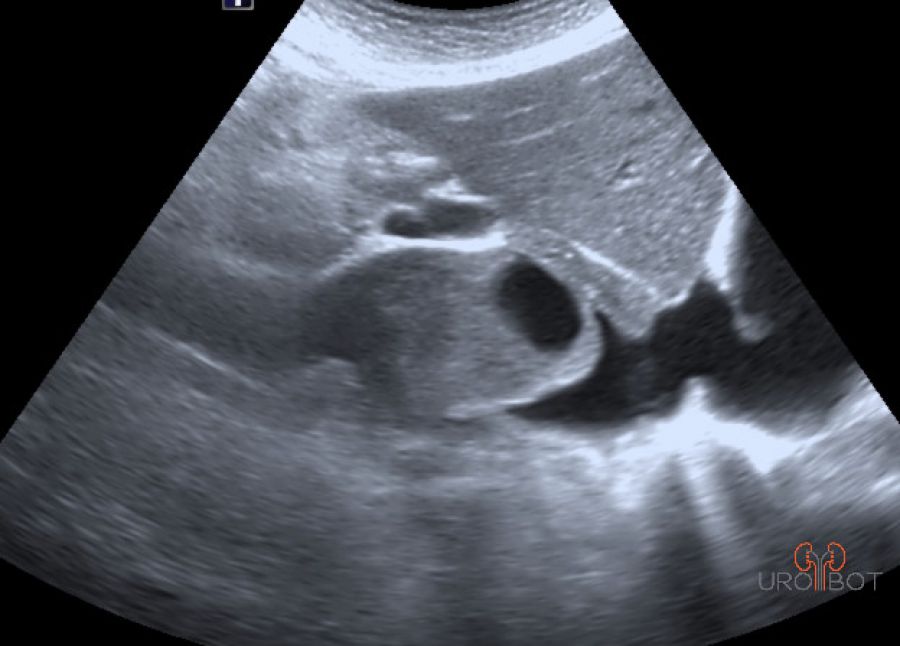

In der Früherkennung ist der Ultraschall die führende Untersuchung. Ab einer Größe von 2 cm kann man bereits bösartige Tumore von gutartigen Zysten unterscheiden. Doch obwohl die Qualität der heutigen Ultraschallgeräte stark zugenommen hat, wird man zu weiteren Unterscheidung und Klassifizierung radiologische Verfahren wie die CT (Computertomographie) oder aber die MRT (Magnetresonanztomographie) einsetzen.

Das Video zeigt eine sonographische Untersuchung der rechen Seite mit Nachweis eines großen Tumorthrombus in der unteren Hohlvene.